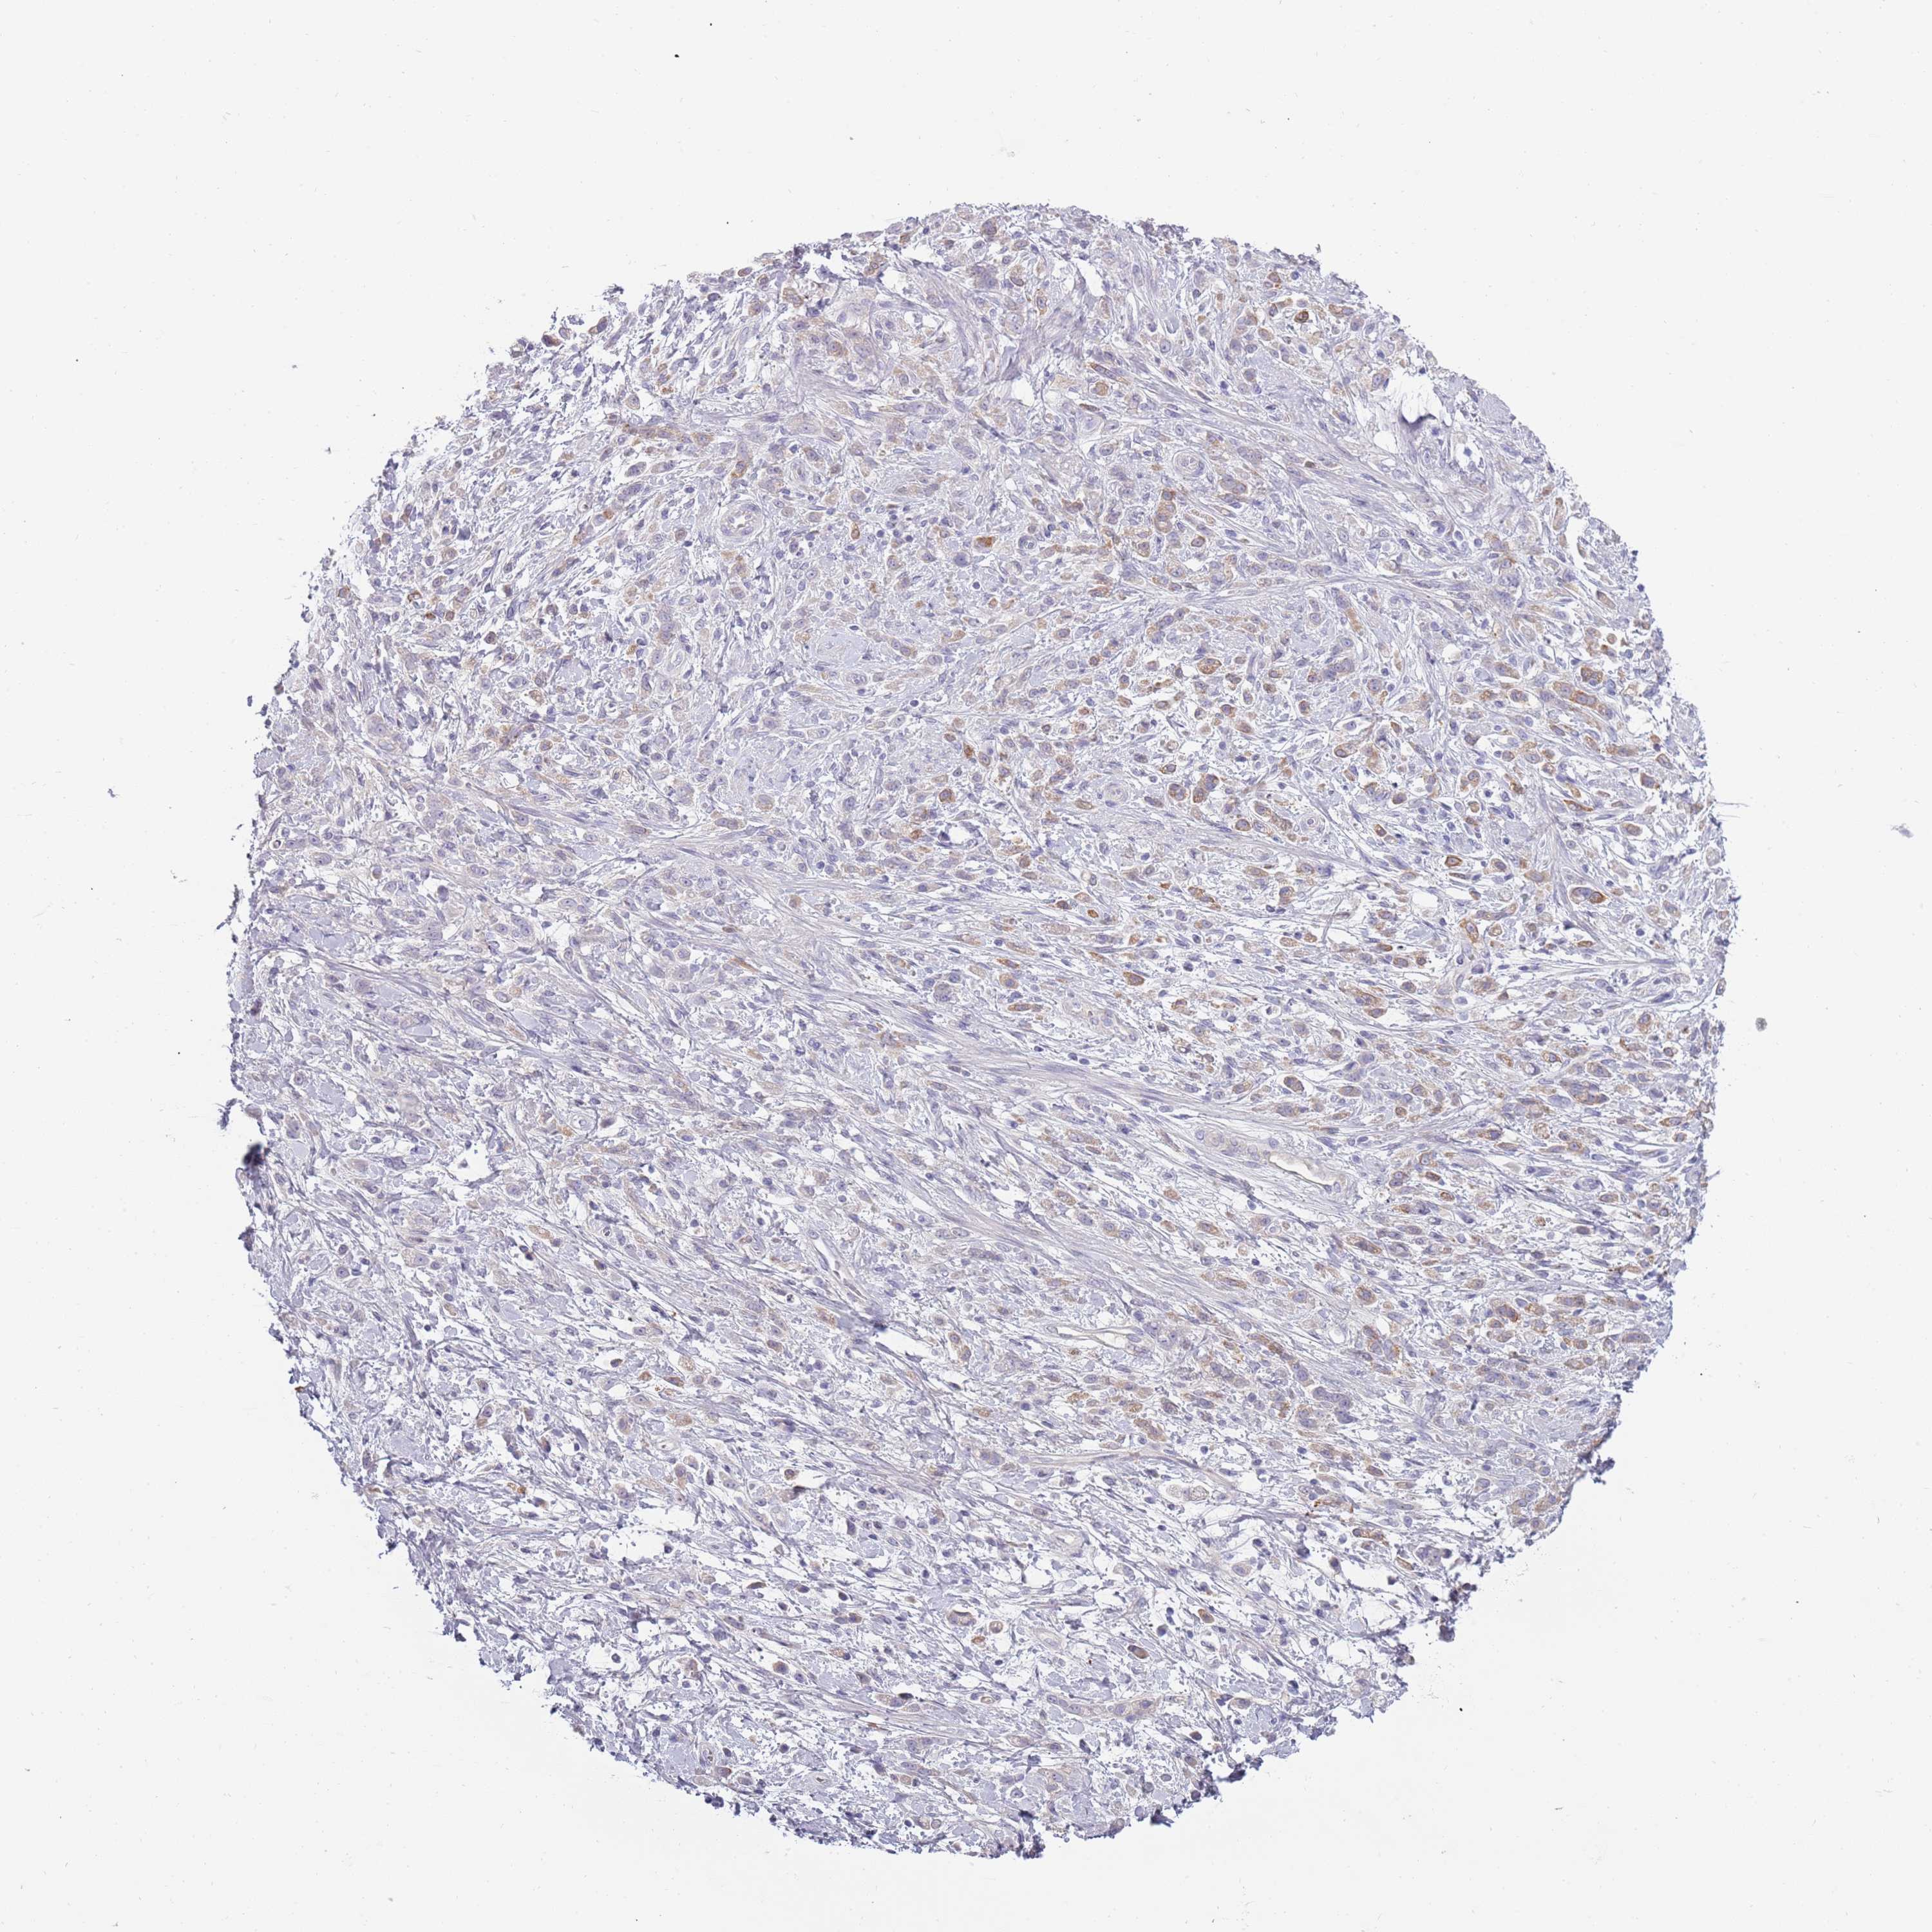

STOMACH CANCER - Protein expressioni

A mouse-over function shows sample information and annotation data. Click on an image to view it in a full screen mode. Samples can be filtered based on level of antibody staining by selecting one or several of the following categories: high, medium, low and not detected. The assay and annotation is described here.

Note that samples used for immunohistochemistry by the Human Protein Atlas do not correspond to samples in the TCGA dataset.

Antibody stainingi

Antibody staining in the annotated cell types in the current human tissue is reported as not detected, low, medium, or high, based on conventional immunohistochemistry profiling in selected tissues. This score is based on the combination of the staining intensity and fraction of stained cells.

Each image is clickable and will lead to virtual microscopy that enables deeper exploration of all samples and also displays staining intensity scores, fraction scores and subcellular localization as well as patient and tissue information for each sample.

Antibody HPA047154

Staining

High

Medium

Low

Not detected

Intensity

Strong

Moderate

Weak

Negative

Quantity

>75%

75%-25%

<25%

None

Location

Nuclear

Cytoplasmic/membranous

Cytoplasmic/membranous,nuclear

Adenocarcinoma, NOS